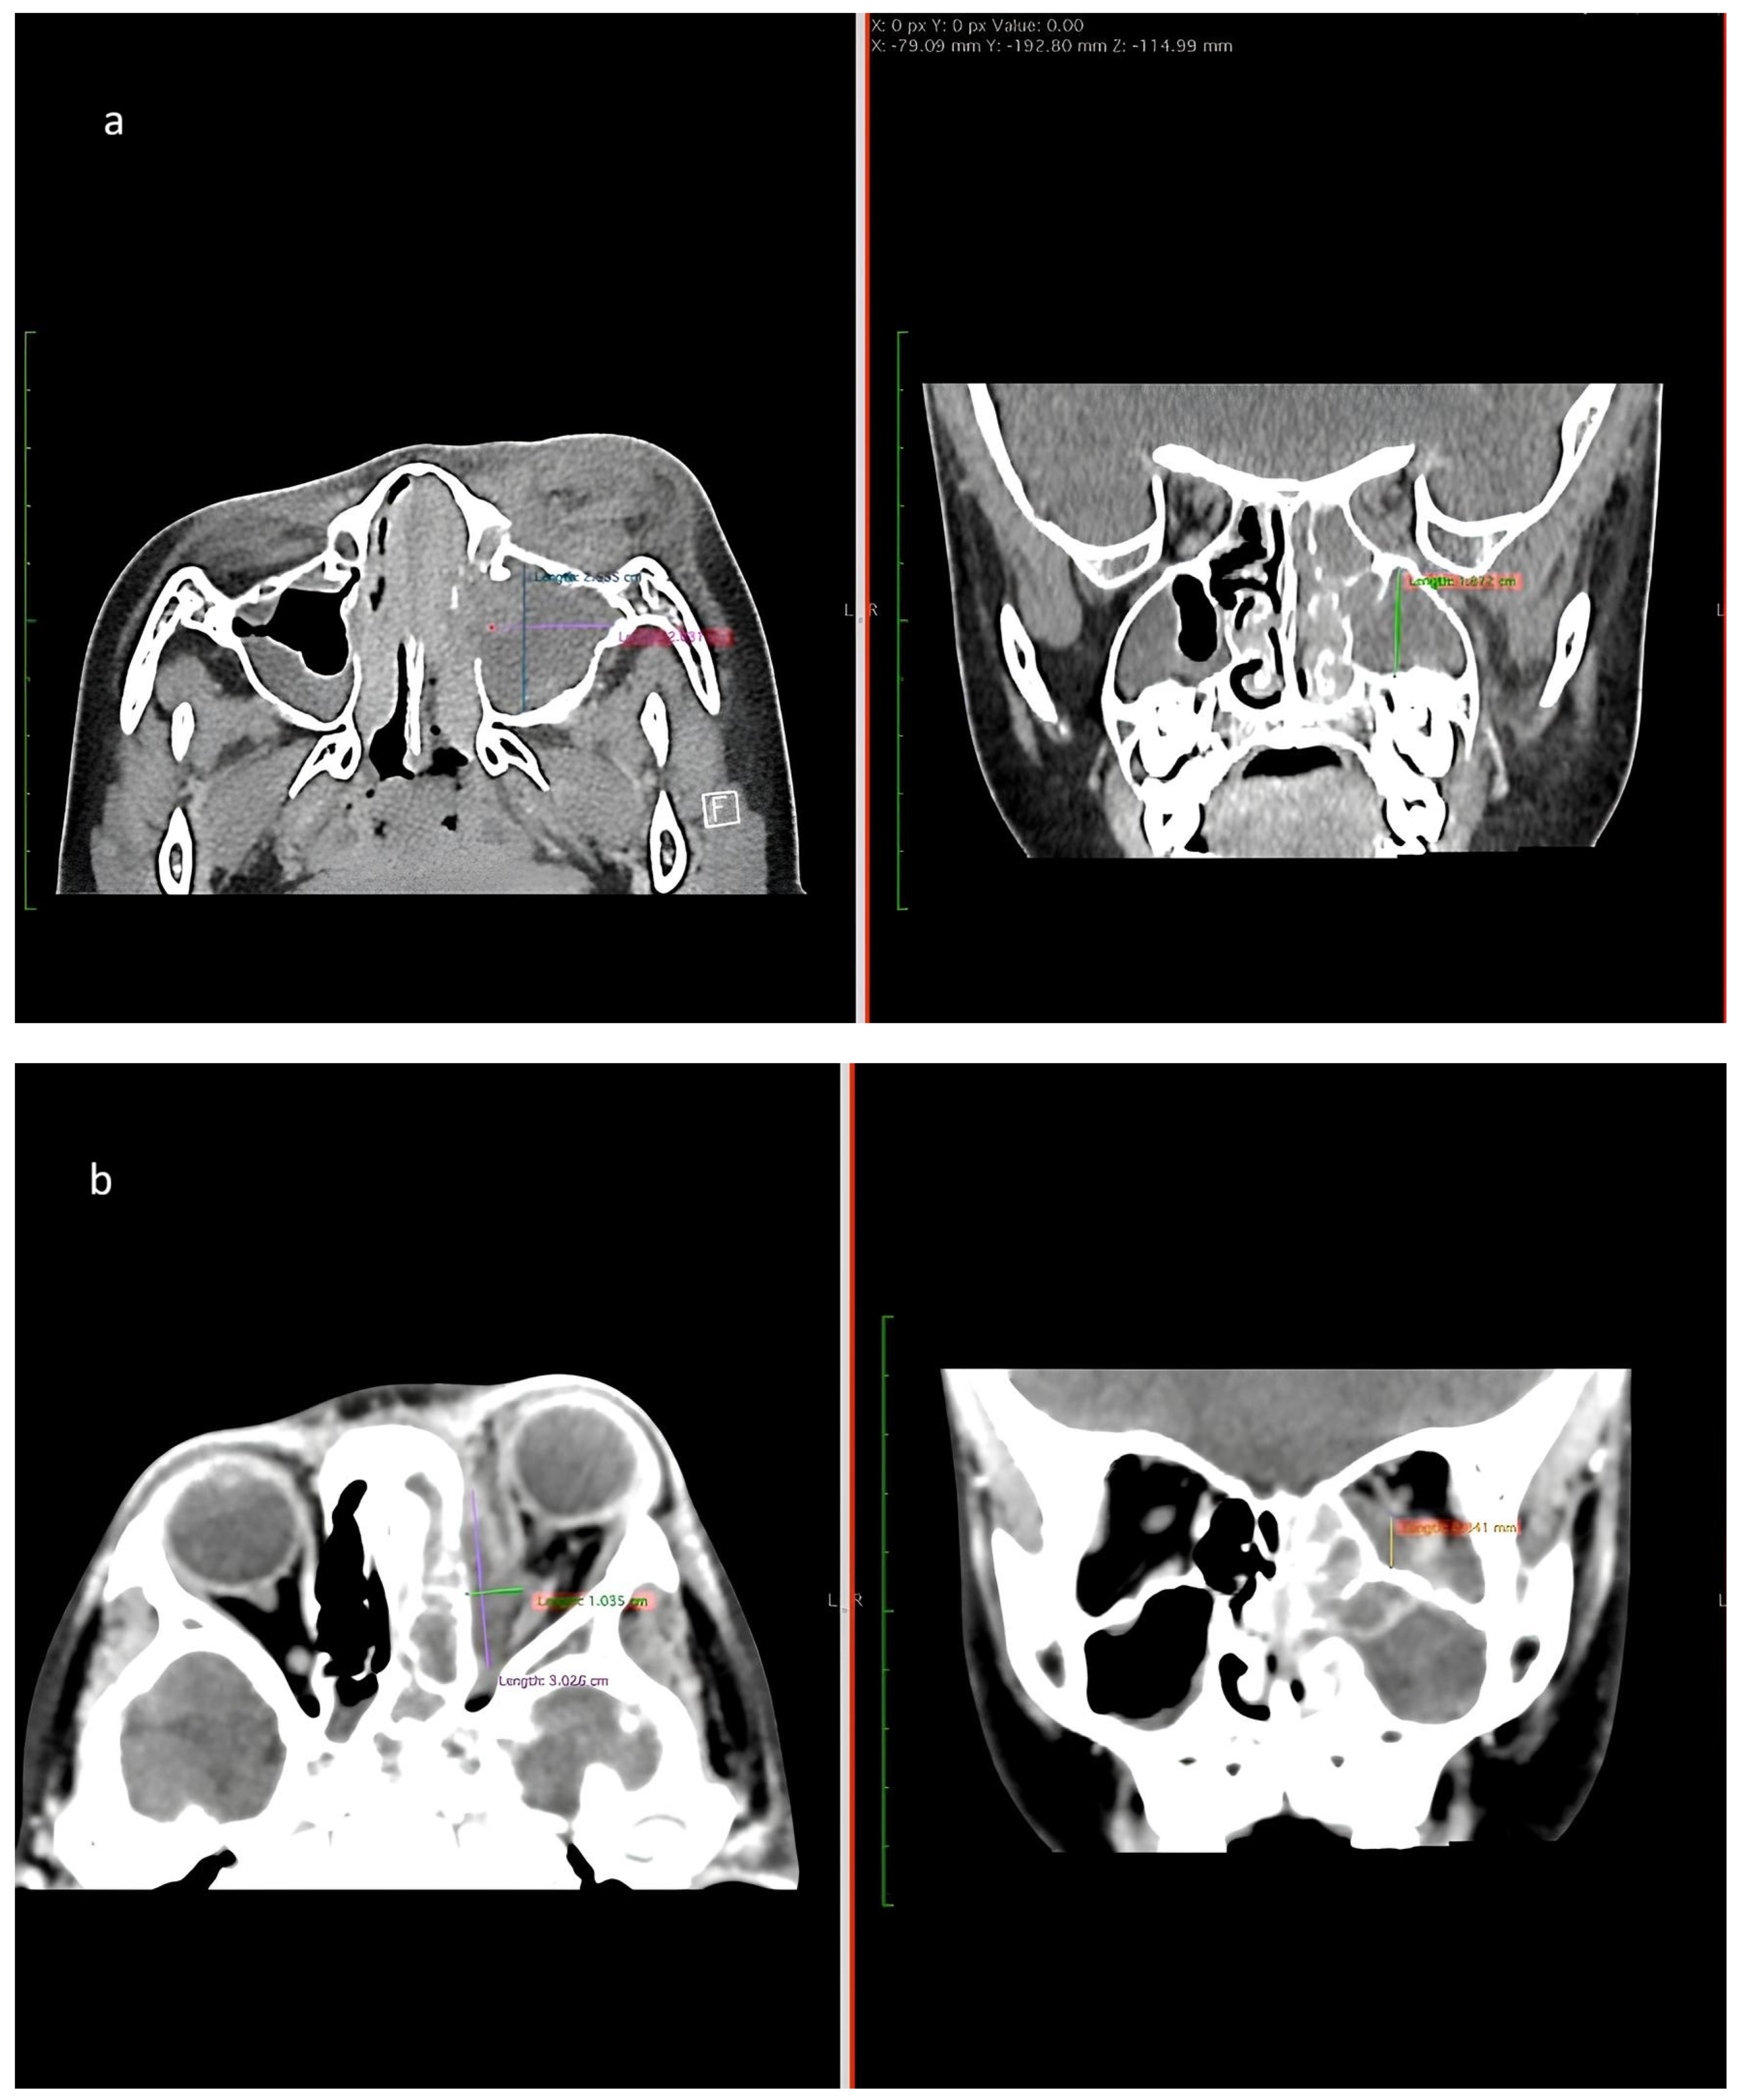

Figure 3. (a) CT of paranasal sinus shows intrasinus collection collectively measures approximately 2.5 cm × 2.0 cm × 1.9 cm (Anteroposterior × Width × Craniocaudal). (b) CT image shows rim-enhancing collection at the left subperiosteal region measuring 3.0 cm × 1.0 cm × 1.8 cm (Anteroposterior × Width × Craniocaudal).

Upon examination, the patient appeared lethargic, with proptosis of the left eye, periorbital swelling, erythema, and restricted eye movement. The pupils were bilaterally reactive. A mucopurulent discharge was observed coming from his left nostril (Figure 2). A high-resolution CT scan revealed a complete opacification of the left ethmoidal, maxillary, and sphenoidal sinuses, with rim enhancement seen within. A soft tissue density is present in the left nasal cavity with obliteration of the osteomeatal complex. There was associated erosion of the left lamina papyracea. Fat stranding is seen involving the left medial extraconal space with a rim enhancing collection located at the left subperiosteal region. This causes lateral displacement of the medial rectus muscle (Figure 3). A diagnosis of acute bacterial sinusitis with a subperiosteal abscess was established. He was initiated on intravenous ceftriaxone and metronidazole.